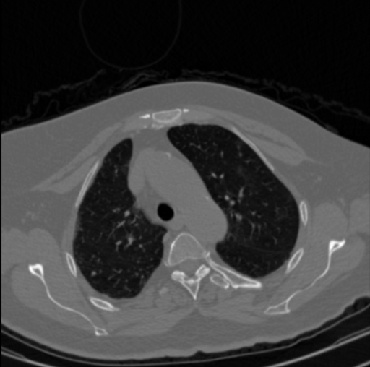

Early and reliable COVID-19 diagnosis based on chest 3-D CT scans can assist medical specialists in vital circumstances. Deep learning methodologies constitute a main approach for chest CT scan analysis and disease prediction. However, large annotated databases are necessary for developing deep learning models that are able to provide COVID-19 diagnosis across various medical environments in different countries. Due to privacy issues, publicly available COVID-19 CT datasets are highly difficult to obtain, which hinders the research and development of AI-enabled diagnosis methods of COVID-19 based on CT scans. In this paper we present the COV19-CT-DB database which is annotated for COVID-19, consisting of about 5,000 3-D CT scans, We have split the database in training, validation and test datasets. The former two datasets can be used for training and validation of machine learning models, while the latter will be used for evaluation of the developed models. We also present a deep learning approach, based on a CNN-RNN network and report its performance on the COVID19-CT-DB database.